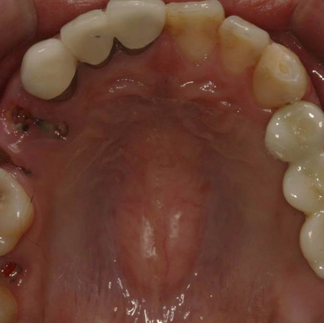

26 year old male patient presented with multiple carious lesions, multiple amalgam fillings, and PFM crowns on #11 & 21.

Pre-operative Observation

2 months after extraction of the tooth #24, 25, 26 and 27.

Extraction site was not completely healed.